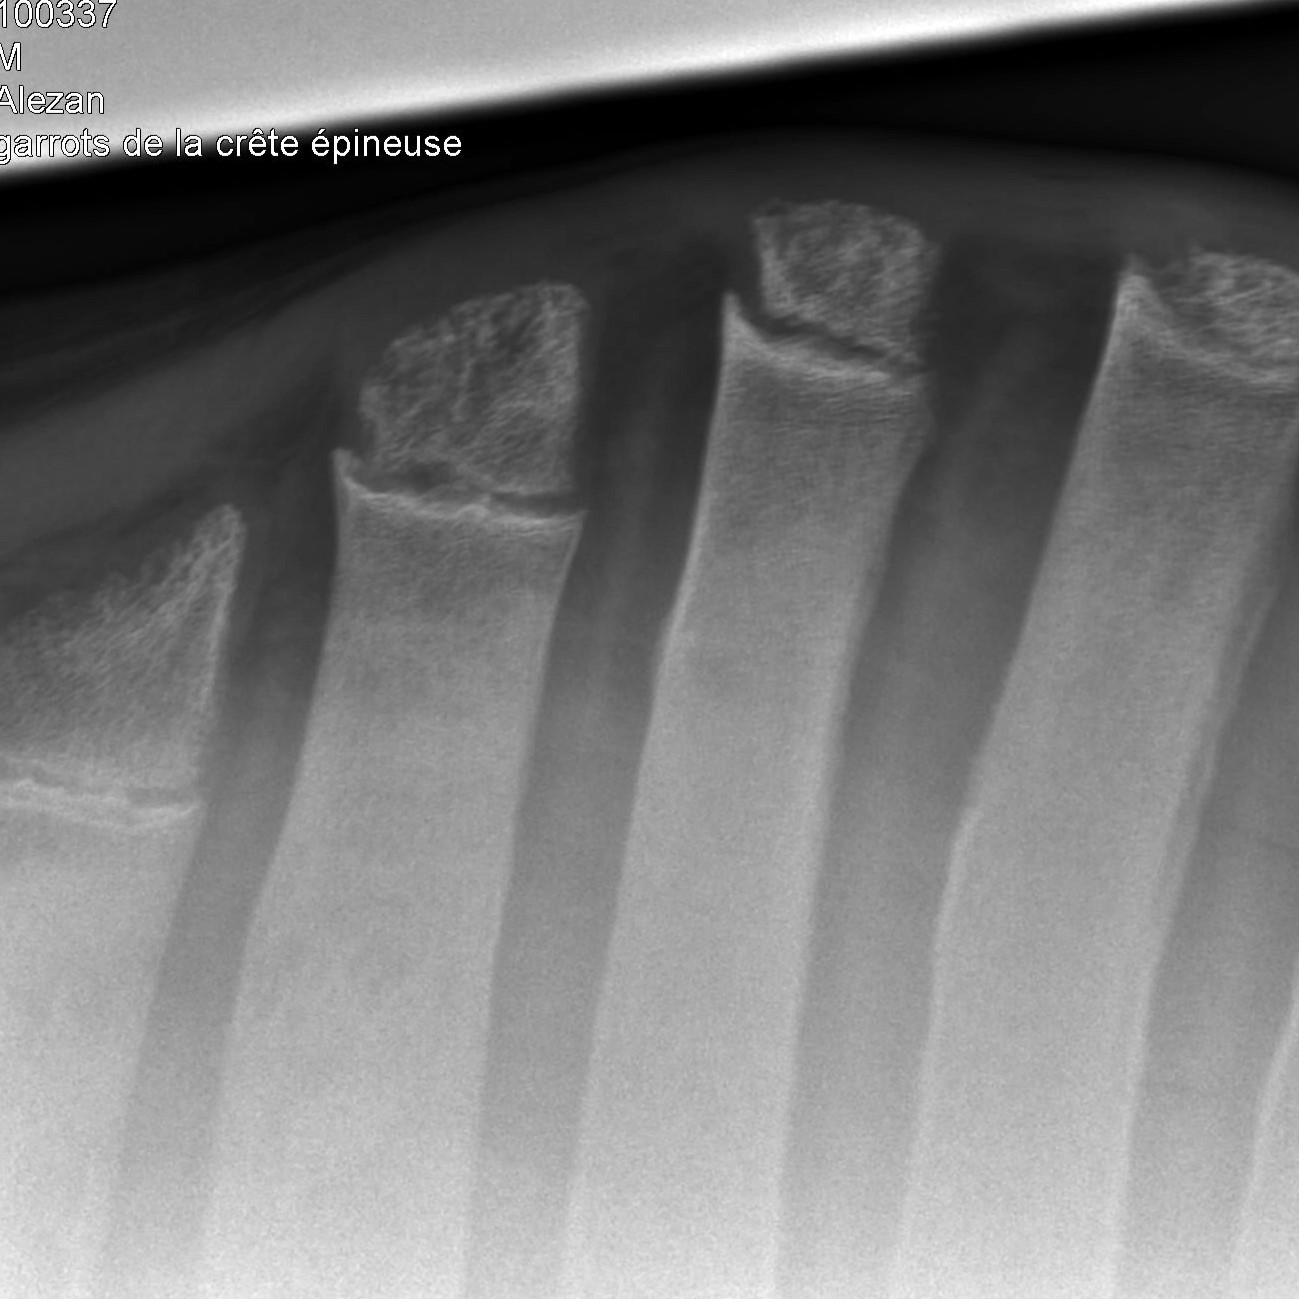

Radiographie des membres

Très utile lors de la recherche de fractures, la radiographie des membres permet également l'évaluation de différents problèmes articulaires tels que l'arthrose ou la dysplasie.

garrot de cheval